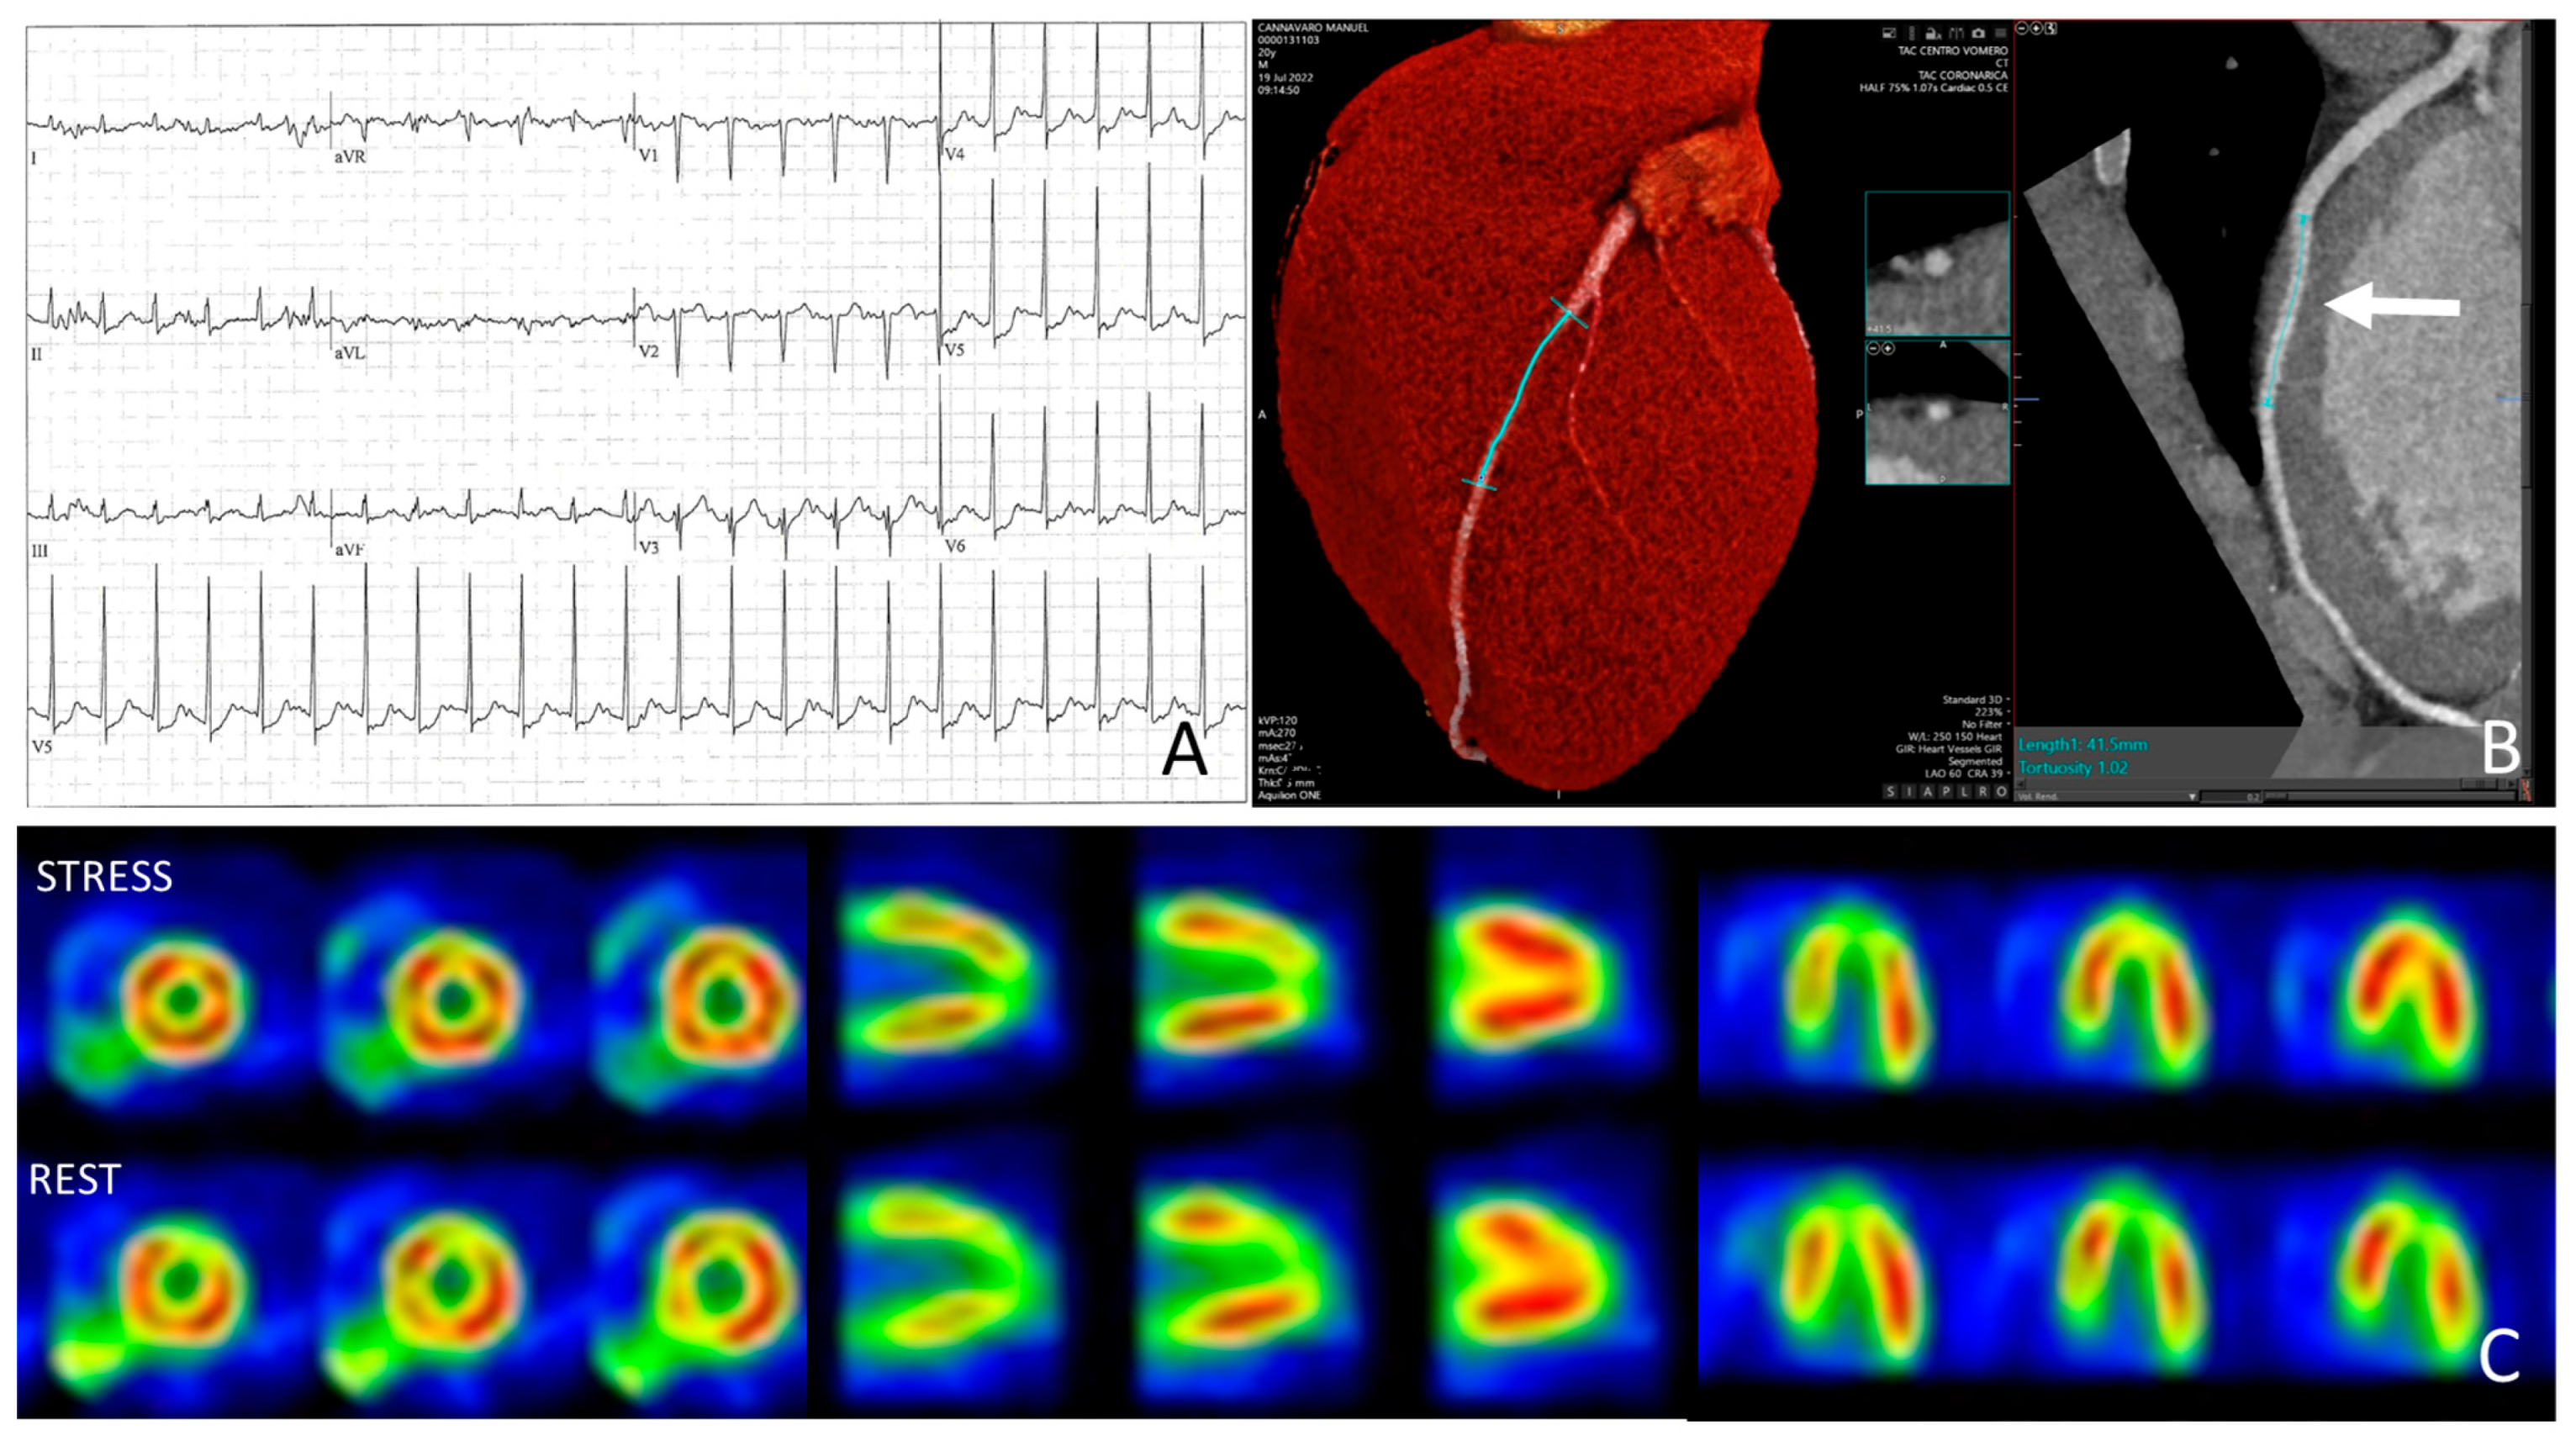

4.2. Athlete with Positive Exercise Testing and Myocardial Bridging

4.3. Athlete with Anomalous Origin of the Coronary Arteries with Interarterial Course